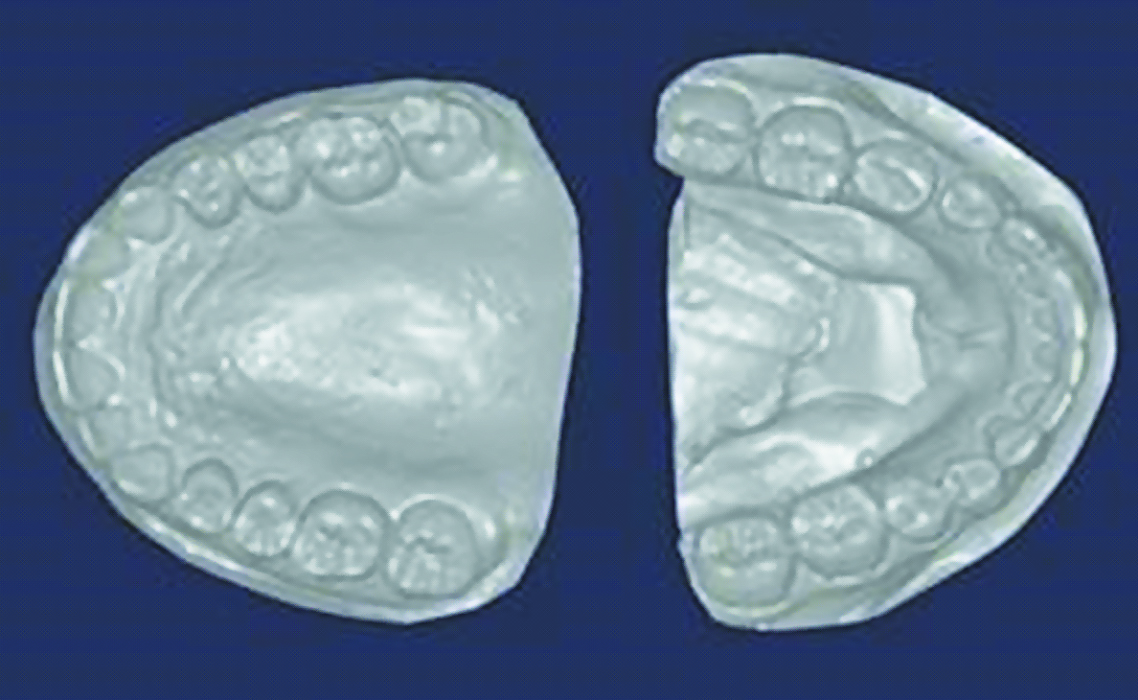

Затем были сняты слепки альгинатной массой для дальнейшего изготовления диагностических гипсовых моделей с их последующим сканированием (рисунок 2).

Рисунок 2. Сканирование гипсовых моделей.

Figure 2. Scanning of plaster models.

Это позволило получить STL-файлы (рисунок 3) для последующей загрузки в разработанную нами компьютерную программу для оценки положения зубов, зубных рядов, окклюзии.

Рисунок 3. STL файлы верхнего и нижнего зубного ряда.

Figure 3. STL files of the upper and lower dental arches.